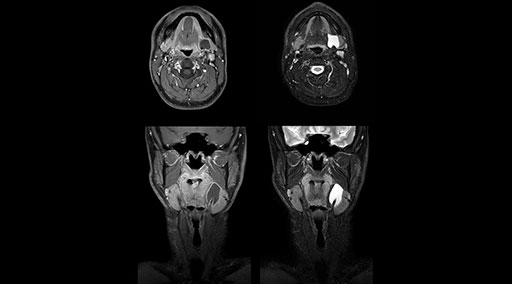

mDIXON TSE fat suppression helps DMG reduce repeats and supports diagnostic confidence

“Our DMG Lisle location includes a cancer center, so soft tissue neck scans, brachial plexus scans, and prostate scans are common. For these exams, mDIXON TSE provides excellent images with and without fat suppression all while helping us reduce repeats and work more efficiently,” Mr. Duffy says.

“With the 2-echo Philips mDIXON TSE the timing is short and the fatsat is very robust. The biggest thing is that you know your fat suppression will be good, even in thin patients or large patients that are off-center,” Mr. Sybesma says.

“Since we work in fixed time slots, not having to repeat scans is key for us,” Mr. Duffy adds. “With mDIXON TSE we get high quality results the first time – unless of course the patient absolutely jumps off the table. For us, that’s significant, because just a single repeat scan could put us behind schedule.

“mDIXON TSE raises our diagnostic confidence with its homogeneous

fat suppression. Neck exams and rheumatology patients are two examples where mDIXON TSE is especially useful,” Dr. Kaakaji says. “For us it’s also an efficiency boost in exams where we need pre and post T1-weighted images with great fat suppression.”